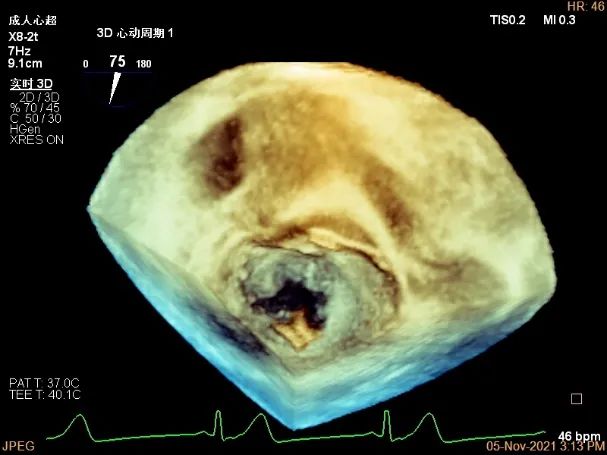

TEE Bicom view:主要脱垂区域为2区

A1P1区后叶发育短小,约5.3mm

A2P2区前后叶长度可,为主要脱垂区域,进而制定手术策略: 2区一个长夹子解决脱垂主要病变区域